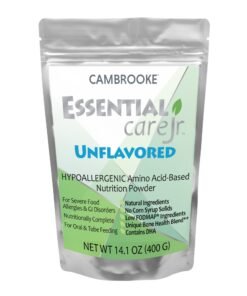

$27.75